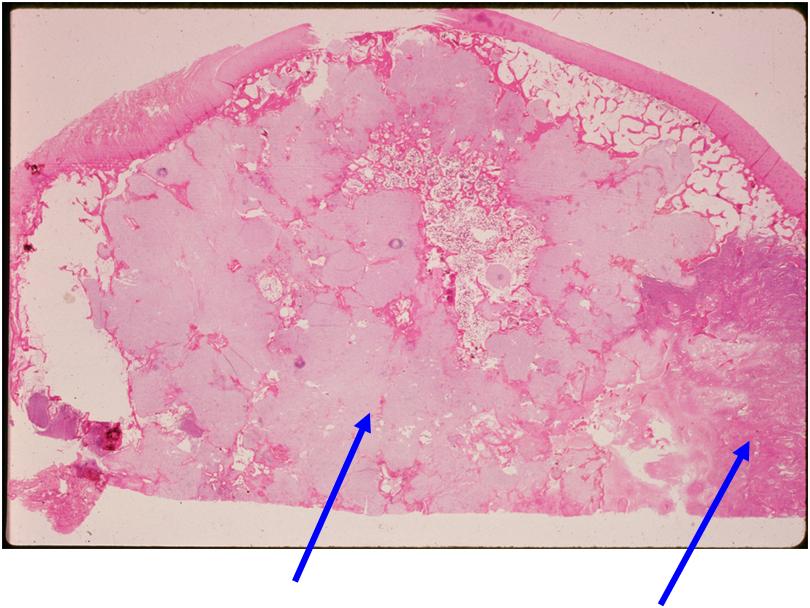

Microscopic Pathology

- Chondrosarcoma component is often grade I (Low Grade Hyaline Type Cartilage)

- Dedifferentiated component

- Predominant noncartilaginous/spindle sarcoma component varies

- Fibrosarcoma and MFH most frequently reported

- MFH is a high grade pleomorphic spindle cell tumor with a storiform pattern

Junction of cartilaginous and noncartilaginous components is sharp and distinct. There are no dedifferentiated areas admixed in the middle of the cartilaginous areas

(Right Arrow) Dedifferentiated Component

(Left Arrow) Low Grade Cartilage Component

(Right Arrow) Low Grade Cartilage Component